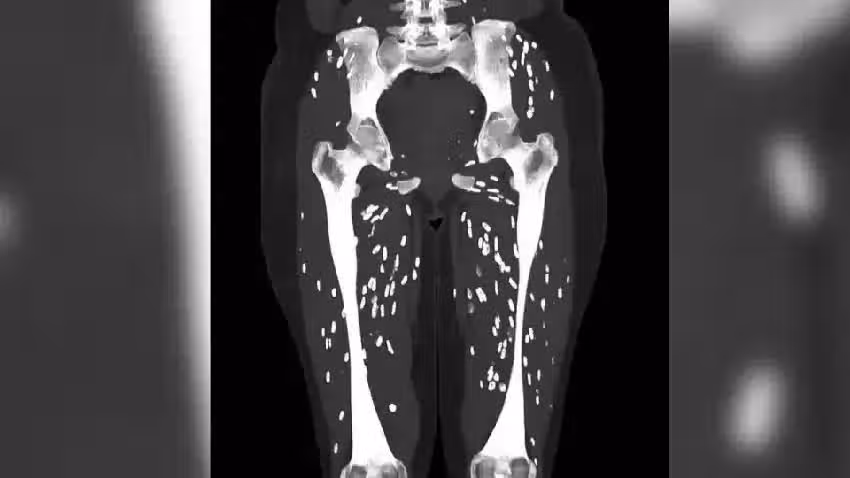

患者因為吃下沒煮熟豬肉,感染了「囊蟲病」,接受CT掃描時,體內布滿了寄生蟲死後留下的鈣化囊腫。

當囊腫進入大腦時,將出現包括頭痛、癲癇發作,以及意識混亂、頭暈,和一種稱為腦積水的致命的病症。

在這些情況下,通常需要手術切除囊腫。

若囊腫到達眼睛,也可能導致視力模糊或受損,引發感染。

醫師加利提醒,囊蟲病復原後,患者通常能夠正常生活,但不幸的是,仍有一些病例可能致命,根據估計,全球每年約有5000萬人感染,其中約5萬人死亡。

他強調,「所以這個故事的寓意是,盡你所能保持清潔,時常洗手,千萬不要吃生的或未煮熟的豬肉。」目前該張驚人CT掃描照,已在X累計高達632萬次查看。